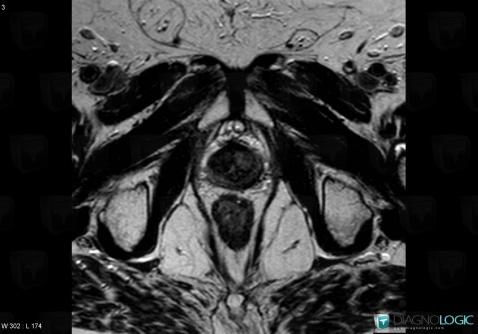

Prostate cancer, Prostate, MRI

Here is the specific information in the key image above:

- Diagnosis Prostate cancer, Location(s) Prostate, with gamuts T2 WI hypointense prostatic lesion